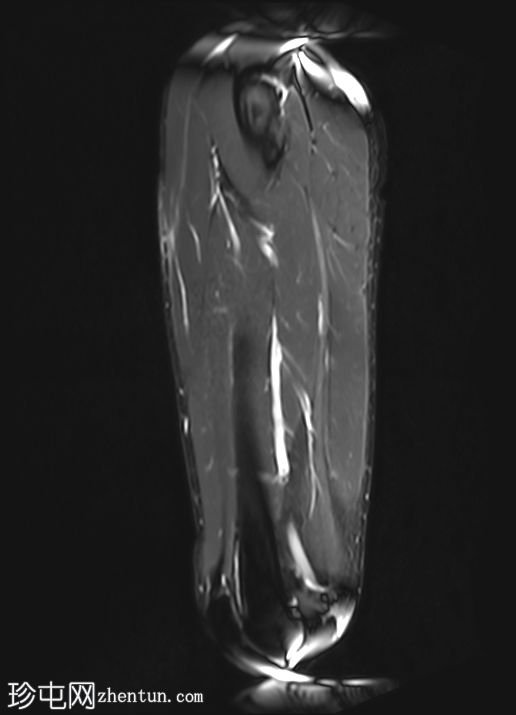

矢状位

T1加权像

股直肌近端和中段前外侧可见一水肿性高信号影,长约15厘米,宽约3厘米。肌纤维轻度分离,但未见撕裂。肌内未见积液;在相邻肌间隙可见一条细小的液线环绕肌肉,延伸至近端肌腱交界处。

股直肌中段的间接肌腱轻度增厚,伴有肌腱周围水肿,提示2B级拉伤。但肌腱保持连续性,骨性附着良好,未见撕裂。